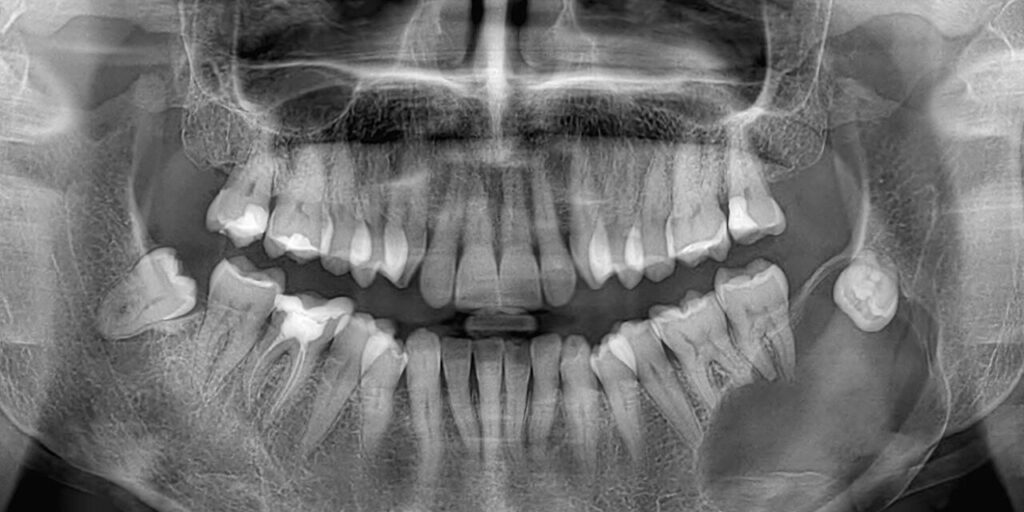

Οι οδοντοφόρες κύστεις απαντώνται συχνότερα σε σχέση με τρίτους γομφίους της κάτω ή άνω γνάθου και κυνόδοντες της άνω γνάθου, οι οποίοι είναι και οι συχνότεροι τύποι έγκλειστων δοντιών.

Η υψηλότερη επίπτωση των οδοντοφόρων κύστεων εμφανίζεται κατά τη δεύτερη και τρίτη δεκαετία της ζωής και έχουν υψηλότερη επίπτωση στους άντρες.

Συνήθως τα συμπτώματα απουσιάζουν, ενώ η καθυστερημένη ανατολή ενός δοντιού είναι η συχνότερη ένδειξη ύπαρξης οδοντοφόρου κύστης. Οι ασθενείς είναι δυνατό να παρατηρήσουν αργά αυξανόμενη διόγκωση. Μια κύστη μπορούσε να φτάσει τα 4-5 εκ. σε διάμετρο σε χρονικό διάστημα 3-4 ετών. Η κύστη είναι δυνατό να φτάσει σε μεγάλες διαστάσεις, ενώ σπάνια φτάνει σε τέτοιο μέγεθος ώστε να προδιαθέτει σε παθολογικό κάταγμα. Σε περίπτωση επιμόλυνσης, η κύστη μπορεί να γίνει επώδυνη.

Μπορεί να παρατηρηθεί ακόμη απορρόφηση των ριζών των παρακείμενων δοντιών, που έχουν ήδη ανατείλει. Φαίνεται μάλιστα πως οι οδοντοφόρες κύστεις εμφανίζουν μεγαλύτερο δυναμικό απορρόφησης παρακείμενων ριζών σε σχέση με άλλα είδη κύστεων, κάτι που αποδίδεται στον ιδιαίτερο ρόλο του οδοντοθυλακίου.